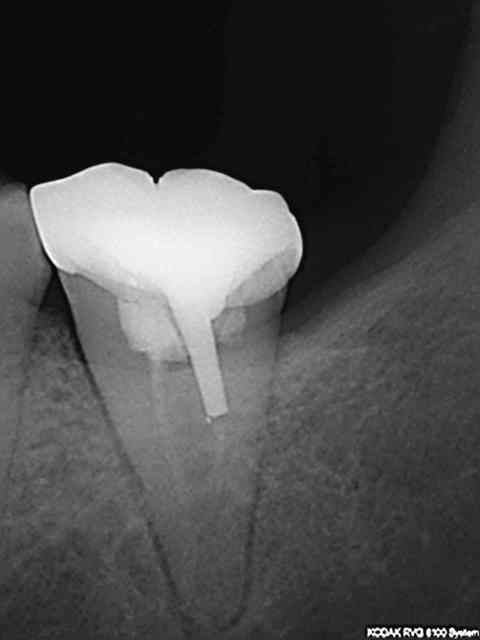

Nouvelle Patiente Mrs X présentant des signes d'appels simultanés sur 36 46. Suspicion d'atteinte pulpaire donc 2 rétro alvéolaires gratuites.-))

Diagnostic : pulpite sur 46 et 4 eme ° sur 36.

Dans le souci de ne pas irradier la patiente inutilement aucune autre radiographie gratuite d'un autre secteur n'est réalisée. Qui plus est le docteur chicot 29 étant équipé d'un capteur kodak 6100 ne peut pas réaliser de mordus rétro coronaires. Le Dr chicot 29 ayant une demi-heure devant lui réalise l'endo de 46 et cote donc Z6 fois 2 + SC 34 et met la patiente sous atb pour le 4 eme de la 36. Ce faisant il fait économiser à la caisse une C à 23 euros.-))

Meme en mode Bw rétro coronaire (capteur horizontal) il est impossible d'avoir toutes les molaires et prémolaires avec un kodak 6100 meme avec 4 clichés (Je ne comprend pas d'ailleurs le capteur semble couvrir toutes les dents) Il manque la 7 ou la 4. 8 clichés sont donc nécessaires (contre 12 en rétro alvéolaires capteur vertical).

Une rétro alvéolaire a été réalisé en sus pour la 37 bien qu'elle ne présente pas de "signes d'appels". Une magnifique endo révélée comme d'hab, le patient est éclairé quant à la survenue d'un éventuel problème. On peut se poser des questions également sur la pertinence des micro classes 1 amalgame sur 46 et 47 a moins que ce soit la conséquence d'un comportement "imaginatif " cher à Catherine M pour rentabiliser les soins opposables.